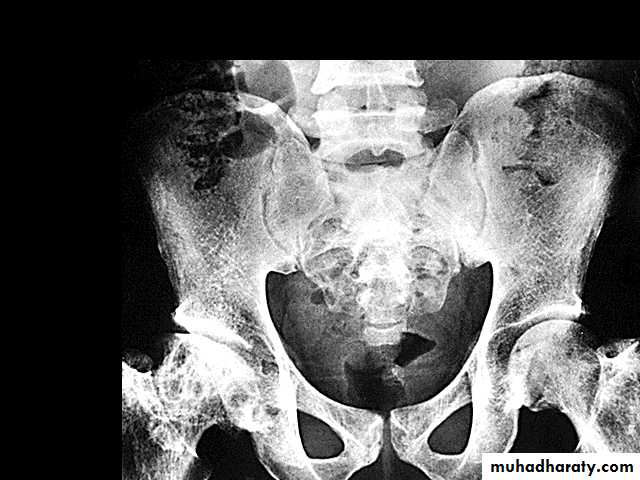

α- thalassemia, gene deletions are responsible for the decrease or absence of α- chains.ß- thalassemia : usually due to an mRNA abnormality.This mutation reduces or eliminates the production of ß-globin chainsClinical manifestations of thalassemiaß- thalassemia major (ßoßo): is the most severe -Becomes apparent 3-6 months after birth when switch from Hb-F to Hb-A takes place :Hepatosplenomegaly (gall stones are also common )Expansion of the bones (hair on end appearance on skull X-ray examination).Severe anaemia with growth retardation and delayed sexual developmentDamage to heart, pancreas, endocrines and liver due to iron over load

The extent to which ß-chain synthesis is suppressed determine the degree of anaemia (ineffective erythropoiesis)Extramedullary hematopoiesis and increased erythropoiesis in the BM lead to over all RBC production is increased due to accumalation of α chain.